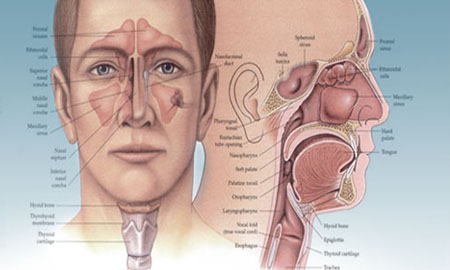

Iniya Hospital specializes in the treatment General Surgery. We have highly skilled personnel, the latest state of the art equipment, and convenient hours. We strive to satisfy every patient’s needs with comprehensive, sensitive, and cost effective care. Treating all kinds of General Surgery, Laparoscopy, General medicine, Neuro Medicine, Paediatric Medicine and Surgery, Surgical Oncology, Plastic Surgery, Urology, Orthopaedics, ENT and Dental, Skin , Physio- Theraphy. All neonatal and paediatric patients are also being treated here.. With you’ll receive the highly qualified care from our warm staff.